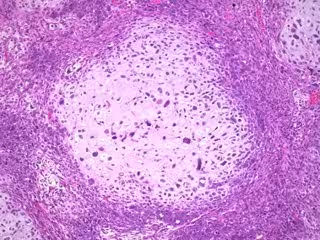

Sufrir un cáncer de mama predispone a desarrollar un cáncer ginecológico

Un estudio elaborado entre los registros de cáncer poblacional de Girona y Tarragona y con la colaboración del Institut Catal d'Oncologia y del Instituto de Investigación Biomédica de Girona (IDIBGI) muestra el riesgo de diferentes tipos de cáncer ginecológico en las mujeres que han sufrido previamente un cáncer de mama.

El estudio consistió en identificar los cánceres ginecológicos --vulva, vagina, cuello uterino, cuerpo uterino y ovario-- que algunas de estas mujeres desarrollaron después de su primer cáncer de mama.

De entre todos los tipos de cánceres ginecológicos, sólo se observó un aumento significativo en el riesgo de cáncer de endometrio --el tipo de cáncer de cuerpo uterino más frecuente-- que se vio incrementado más del doble, un 128%, en comparación al riesgo de tener un cuerpo de útero en la población general.